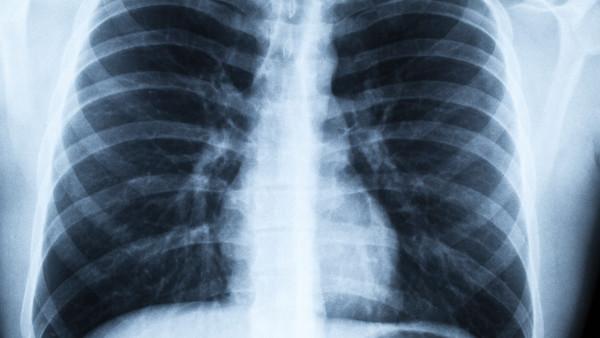

慢性阻塞性肺病(COPD)是一组可以导致呼吸困难的慢性肺部疾病,包括慢性支气管炎和肺气肿。这种病症通常由长期吸烟或接触有害物质引起,严重影响患者的生活质量。尽管COPD是一种无法治愈的疾病,但适当的体力活动可以显著改善患者的生活质量、增强肺功能和提高身体耐力。 体力活动的重要性 1. 改善肺功能:适当的体力活动能够增强呼吸肌肉的力量,提高肺活量。患者在进行有氧运动时,能够增强心肺耐力,改善氧气的摄取和利用。 2. 增加体力和耐力:COPD患者常常感到疲惫,这使得他们难以完成日常活动。规律的体力锻炼能够帮助患者提高体力,降低疲劳感,使其能够更好地应对日常生活中的挑战。 3. 改善心理健康:运动被证明能够缓解抑郁和焦虑,不仅有助于改善患者的情绪,还能增强自信心。COPD患者通过积极参与体育活动,可以获得更好的心理支持。 4. 减少急性发作:规律的体力活动有助于提高免疫系统的功能,从而降低由于感染等因素造成的急性加重发作的风险。 适合COPD患者的体力活动 对于COPD患者,选择合适的体力活动至关重要。以下是一些建议: 1. 有氧运动:如散步、慢跑、游泳和骑自行车等,能够有效提升心肺功能。对于初学者,可以从低强度的活动开始,逐步增加强度和时间。 2. 力量训练:可采用自身体重训练或轻重量训练,帮助增强肌肉力量。力量训练不仅可以提高身体的功能性,还能帮助患者更好地完成日常家务等活动。 3. 柔韧性练习:如瑜伽和拉伸,有助于改善关节的灵活性,增加身体的柔韧性,减轻身体的紧张感。 4. 呼吸训练:通过深呼吸练习和呼吸调节,帮助增强呼吸肌肉的力量,提高气体交换效率。 如何开始 1. 咨询医生:在开始任何锻炼计划之前,COPD患者应咨询医生或专业的康复治疗师,以评估自身的健康状况和适合的锻炼方式。 2. 制定计划:根据个人的喜好和身体状况,制定合理的锻炼计划,并逐步进行调整。可以选择每周进行几次30分钟的有氧运动,并结合力量和柔韧性训练。 3. 保持规律:坚持规律的锻炼习惯,哪怕是每次短时间的活动,积累下来也会产生积极的效果。 4. 寻找支持:参与支持小组或与家人朋友一起锻炼,可以增加运动的乐趣和动力。 结论 慢性阻塞性肺病对患者的生活影响深远,但通过适当的体力活动,患者可以显著改善自身的健康状况和生活质量。通过有意识地进行锻炼,不仅能够改善身体机能,还能提高心理健康。无论是散步还是力量训练,每一点努力都能为生活注入新的活力。希望每位COPD患者都能找到适合自己的运动方式,迈向更健康的未来。